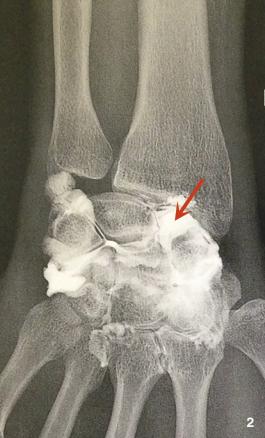

L’arthroscanner bien qu’invasif fournit une exploration fine et dépiste une éventuelle fracture ostéochondrale associée. Surtout, il montre l’importance de la déchirure ligamentaire.³ La fuite du liquide de contraste entre la médiocarpienne et la radiocarpienne signe le diagnostic (fig. 2).¹ ³

La dislocation scapholunaire est responsable d’une réduction de la surface de contact entre le scaphoïde et le radius entraînant précocement une arthrose radioscaphoïdienne qui évolue à plus ou moins long terme vers l’arthrose intercarpienne. En l’absence de traitement et après plusieurs années s’installe une arthrose pancarpienne qui se manifeste par une raideur douloureuse.